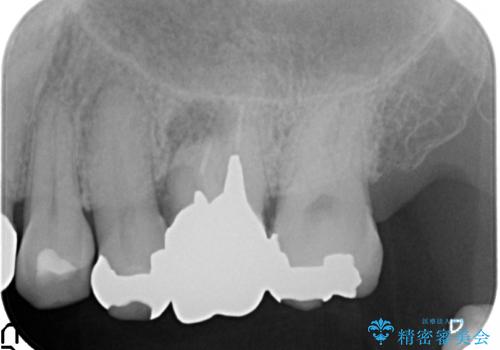

- 左上6番目の歯が疼くので診て欲しいといらっしゃった方の症例です。

左上6のクラウン及びコアを除去したところ、歯根が破折していたため抜歯し、ブリッジによる補綴を行いました。